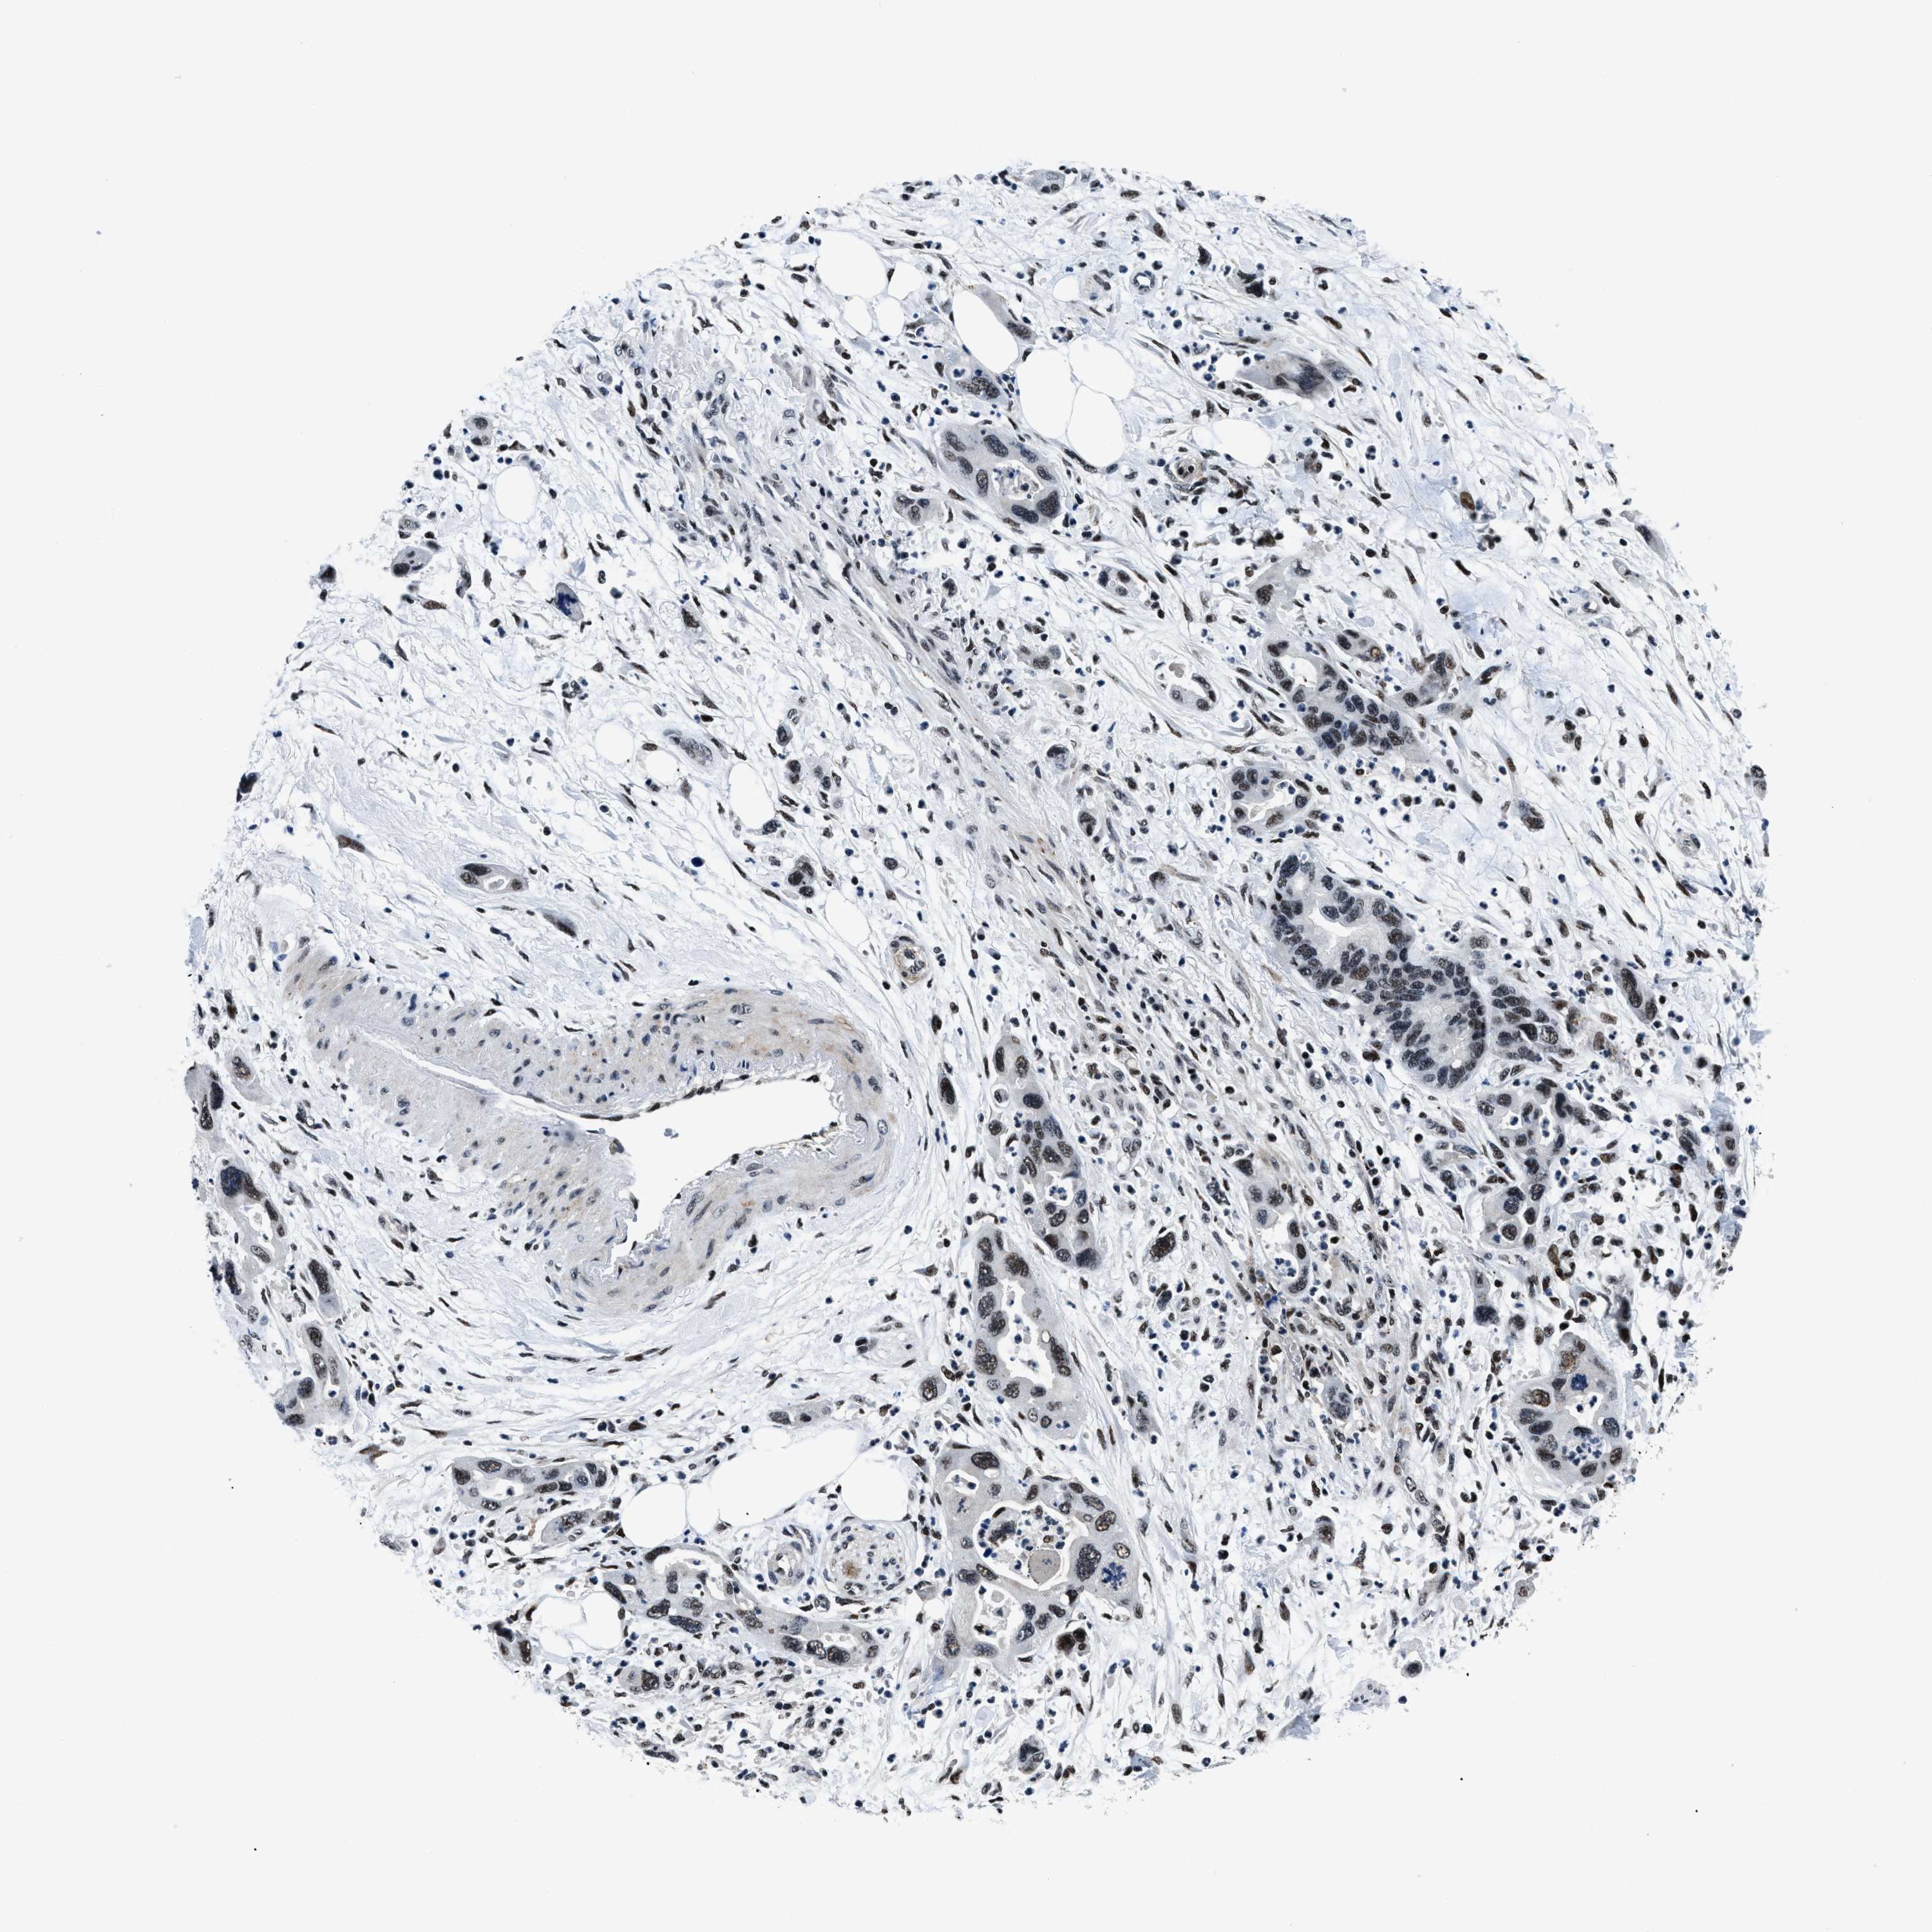

PANCREATIC CANCER - Protein expressioni

A mouse-over function shows sample information and annotation data. Click on an image to view it in a full screen mode. Samples can be filtered based on level of antibody staining by selecting one or several of the following categories: high, medium, low and not detected. The assay and annotation is described here.

Note that samples used for immunohistochemistry by the Human Protein Atlas do not correspond to samples in the TCGA dataset.

Antibody stainingi

Antibody staining in the annotated cell types in the current human tissue is reported as not detected, low, medium, or high, based on conventional immunohistochemistry profiling in selected tissues. This score is based on the combination of the staining intensity and fraction of stained cells.

Each image is clickable and will lead to virtual microscopy that enables deeper exploration of all samples and also displays staining intensity scores, fraction scores and subcellular localization as well as patient and tissue information for each sample.

Antibody HPA018248

Antibody HPA019127

Antibody CAB009196

Staining

High

Medium

Low

Not detected

Adenocarcinoma, NOS

Adenocarcinoma, metastatic, NOS